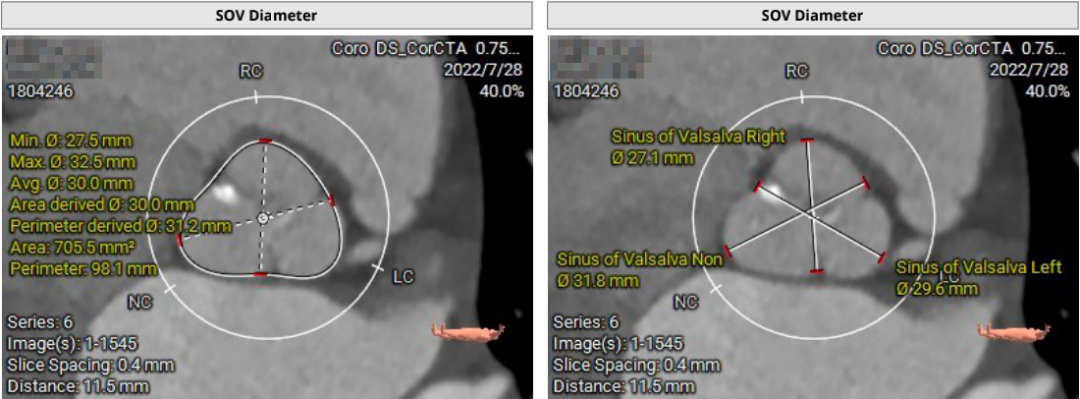

患者71岁女性,诊断为主动脉瓣重度狭窄合并心功能不全,瓣口面积仅0.5cm²,跨瓣压差超过50mmHg,且EF仅27%,心功能极差。术前CT检查瓣环周长72.2mm,LVOT呈喇叭型。CT检查同时发现患者入路血管狭窄,股动脉直径5.3cm,锁骨下和颈内动脉直径都小于5.0cm,对操作造成了一定困难。

结合充分的术前讨论,和策略制定。术中团队建立双侧股动脉入路,以右股为主,使用18F球囊预扩张时未出现腰征,微量反流,因此选择植入24F瓣膜。由于LVOT呈喇叭型,心夹角偏大,最初选择-1mm释放,在释放过程中稍有位移,最终固定在0位,瓣膜充分展开,形态和位置都很好,术后跨瓣压差7-8mmHg,无反流,手术顺利完成。